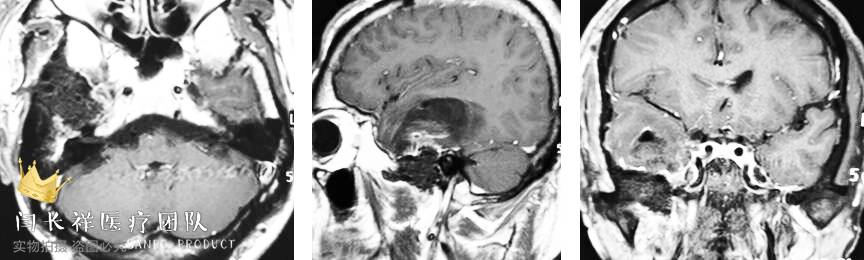

术后6小时复查头部CT示肿瘤切除满意。

中颅窝-颞下窝占位

术后头部增强MRI示肿瘤切除满意。